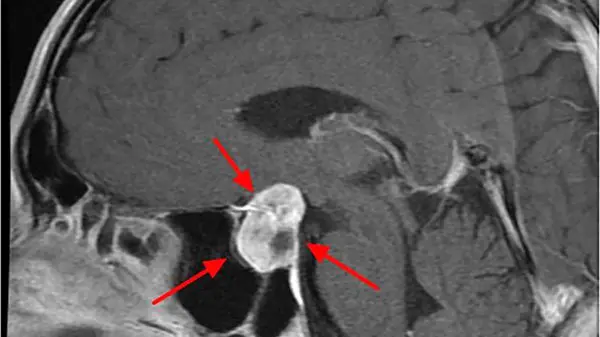

رایج ترین نوع تومور های غده هیپوفیز، آدنوم یا همان ورم هیپوفیز است؛ یک تومور غیر سرطانی که بر روی غده مذکور شکل می گیرد.

اگر آن ها در اندازه یک سانتی متر یا بیشتر باشند، به آن ها ماکروآدنوم می گویند. اما اگر کوچک تر از یک سانتی متر باشند به آن ها میکرو آدنوم می گویند.

تومور هیپوفیز معمولا در حین انجام آزمایشات و درمان مشکلات غیر مرتبط و معمولا در ناحیه مغز و سر تشخیص داده می شوند.

در این شرایط، ممکن است تومور هیپوفیز در نتایج سی تی اسکن از مغز دیده شود؛ آن هم به این خاطر که بیمار به دلیل مشکل سکته احتمالی به اورژانس رفته باشد.